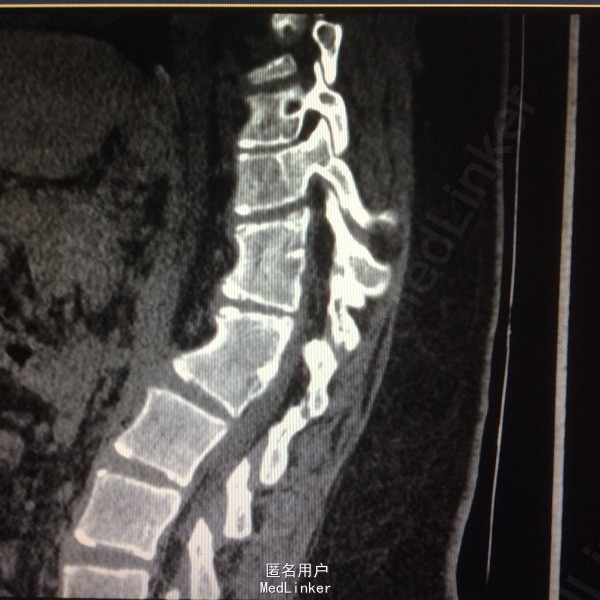

患者呈向心性肥胖,眼角略上斜,下颌小,上下牙间距大,闭齿音发音不清,性早熟,外阴幼稚,大小阴唇发育不良,手脚小胖,指端纤细,余查体无明显异常。 辅助检查:胸9-10胸12-腰1椎体融合、胸11呈半椎体,椎管内脊髓未见明显信号异常.

胸椎半椎体畸形 左侧第10肋骨缺如 隐形骶椎裂 双下肢膝外翻 双下肢肌挛缩症 脊柱畸形术,胸5、6、8、9腰1-2-3双侧椎弓根螺钉,去除胸11-12后方椎板,胸12半椎体及上下间隙间盘去除,椎间隙植骨。

本患者后凸可能是由于机制未明的神经肌肉病变,也可能是脊柱矢状位失平衡结果,若是前者导致可能会出现屈伸脊柱的平衡肌群肌张力或肌力增强或减弱,使融合后上下端再次出现冠状面或矢状面失平衡,需再次手术治疗,密切随访患者病情。